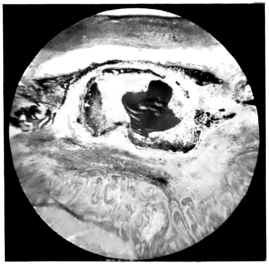

PLATE IV.

22.

LENS DISLOCATED BEHIND RETINA

curly bracket span

48

23.

FISTULA OF THE CORNEA

24.

CAPSULO-CORNEAL SYNECHIA

25.

RETINO-CORNEAL SYNECHIA

26.

SCLERAL FISTULA

27.

"    " (MAGNIFIED)